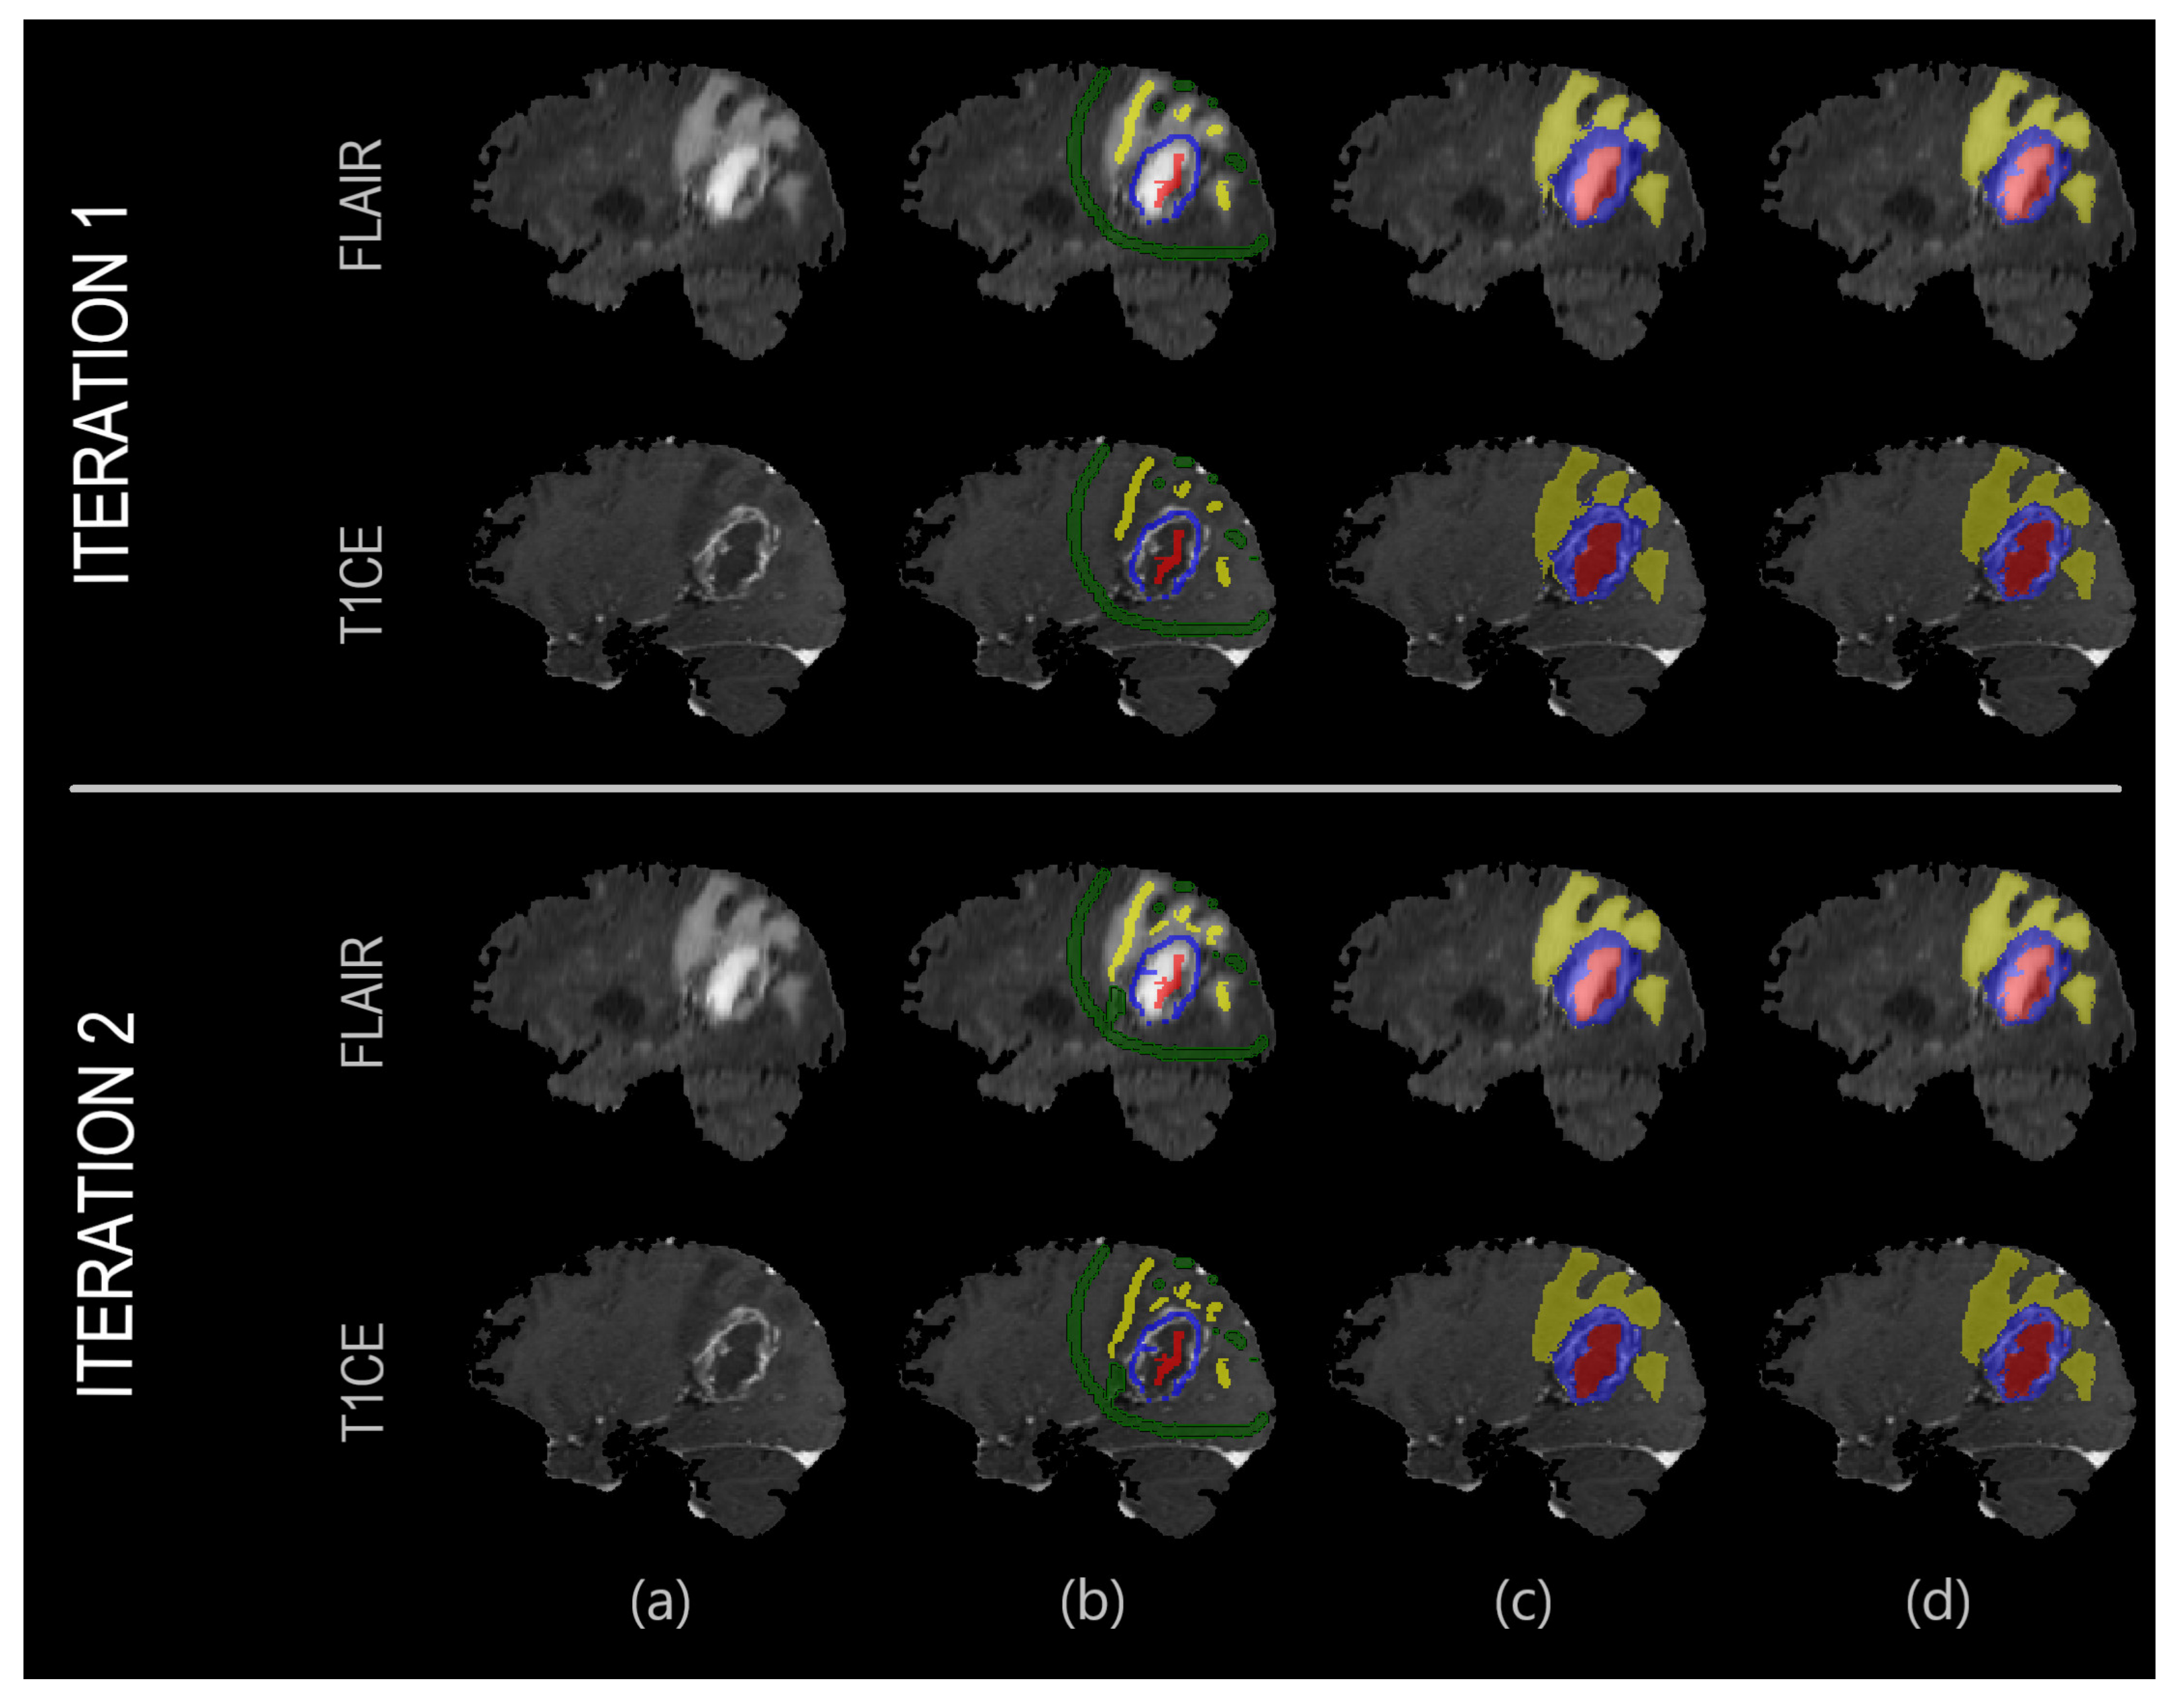

2.2. Proposed Segmentation Algorithm

3.1. Experiment 1: Overall Performance Evaluation